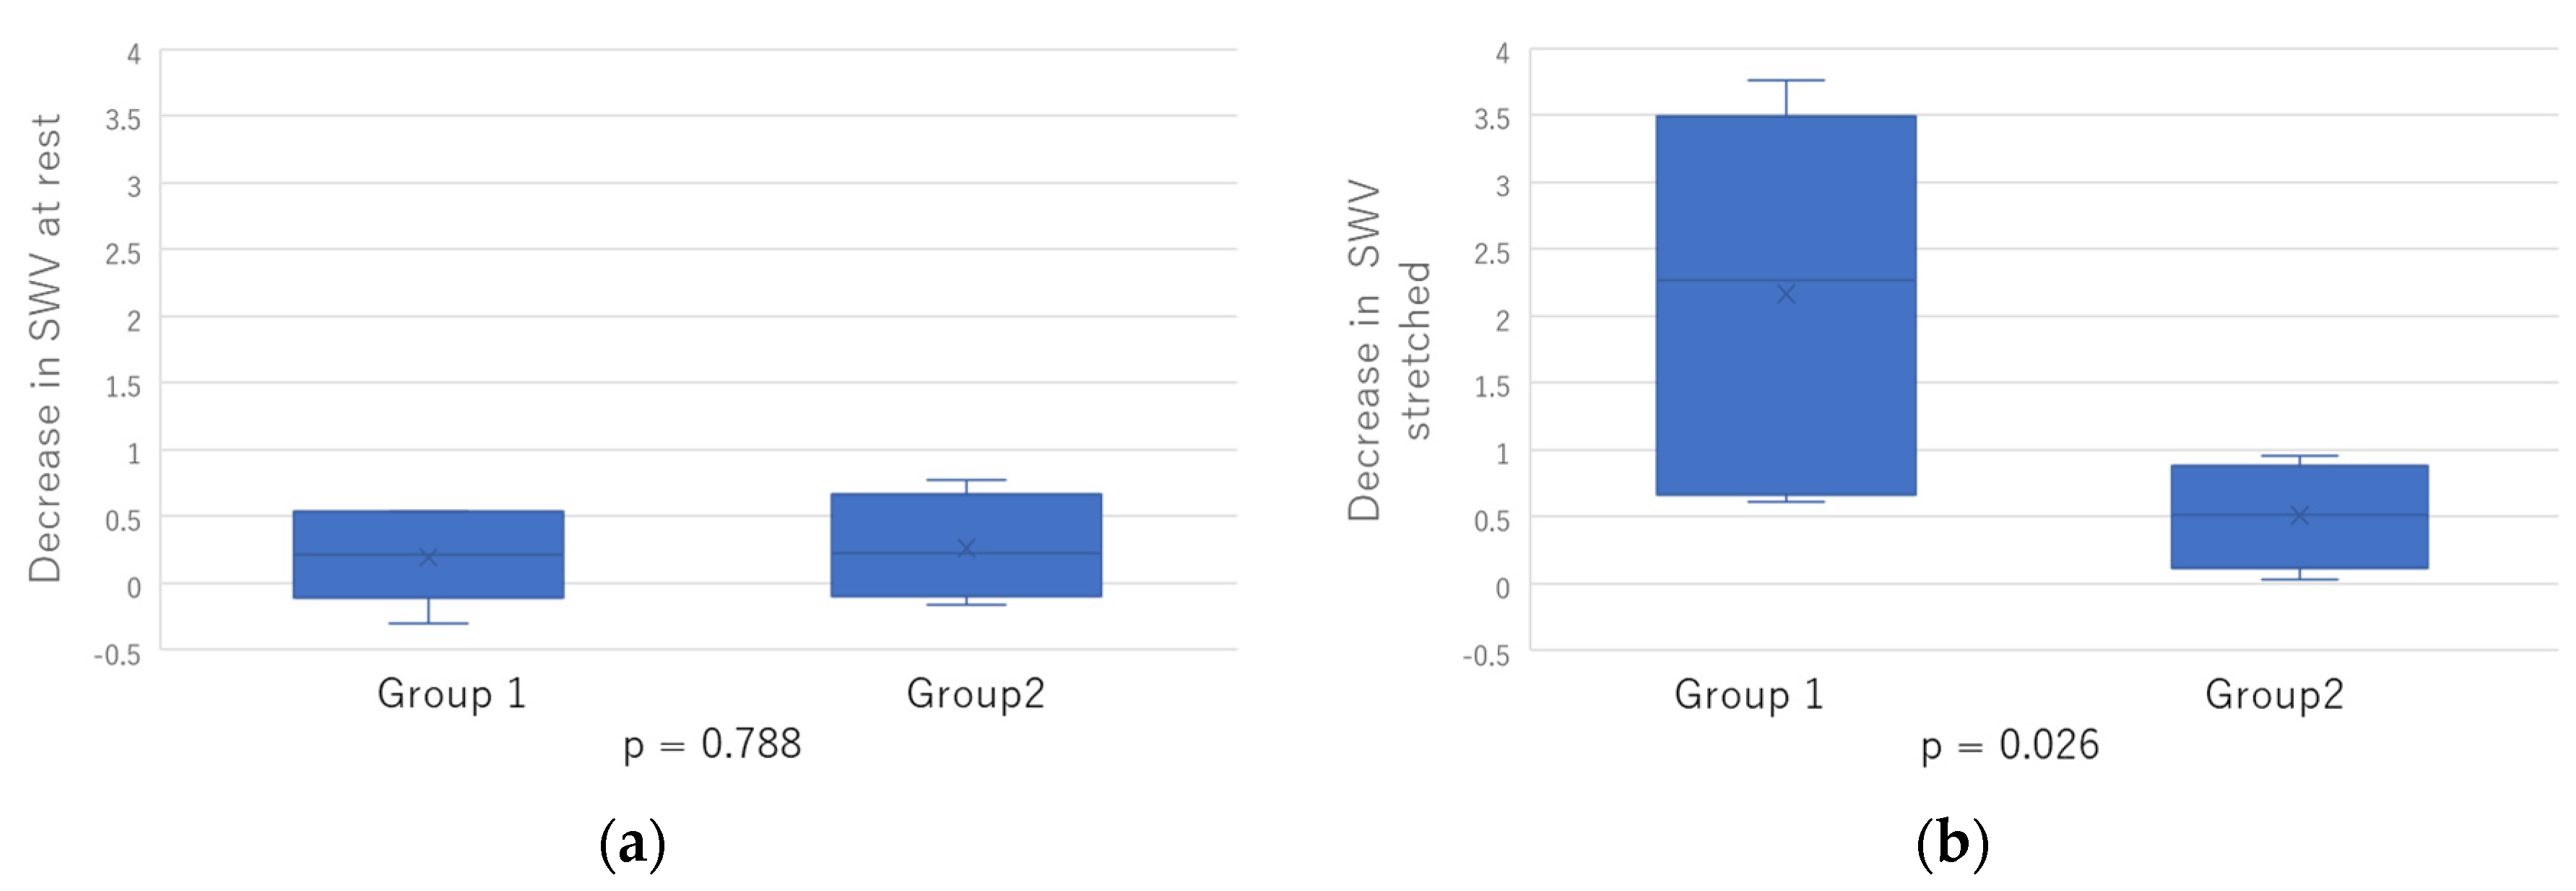

2.3. Comparison between Two Groups

| ROM changes after treatment: (Group 1) no change; (Group 2) change. | |

| Group1/2 | 6/4 |